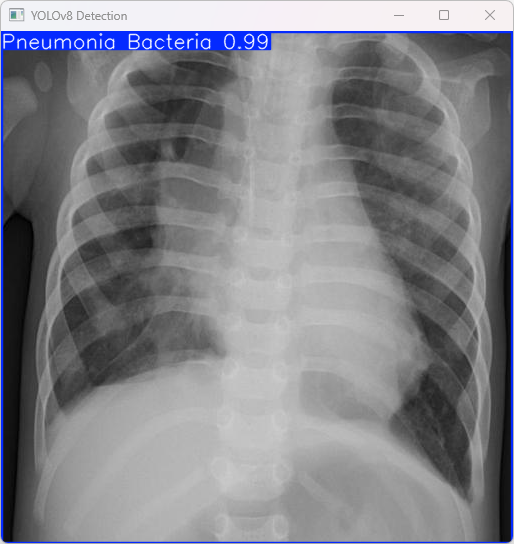

执行imgTest.py代码后,会将执行的结果直接标注在图片上,结果如下:

这段输出是基于YOLOv8模型对图片“imagetest.jpg”进行检测的结果,具体内容如下:

图像信息:

(1)处理的图像路径为:TestFiles/imagetest.jpg。

(2)图像尺寸为640×640像素。

检测结果:

(1)检测到图像属于 “Pneumonia Bacteria” 类别(细菌性肺炎)

处理速度:

(1)预处理时间: 7.0 毫秒

(2)推理时间: 4.5 毫秒

(3)后处理时间: 63.8 毫秒

总结:

模型成功识别图像中的肺炎类型为细菌性肺炎,并且推理过程高效。此系统适合快速诊断图像,具有实际应用潜力。